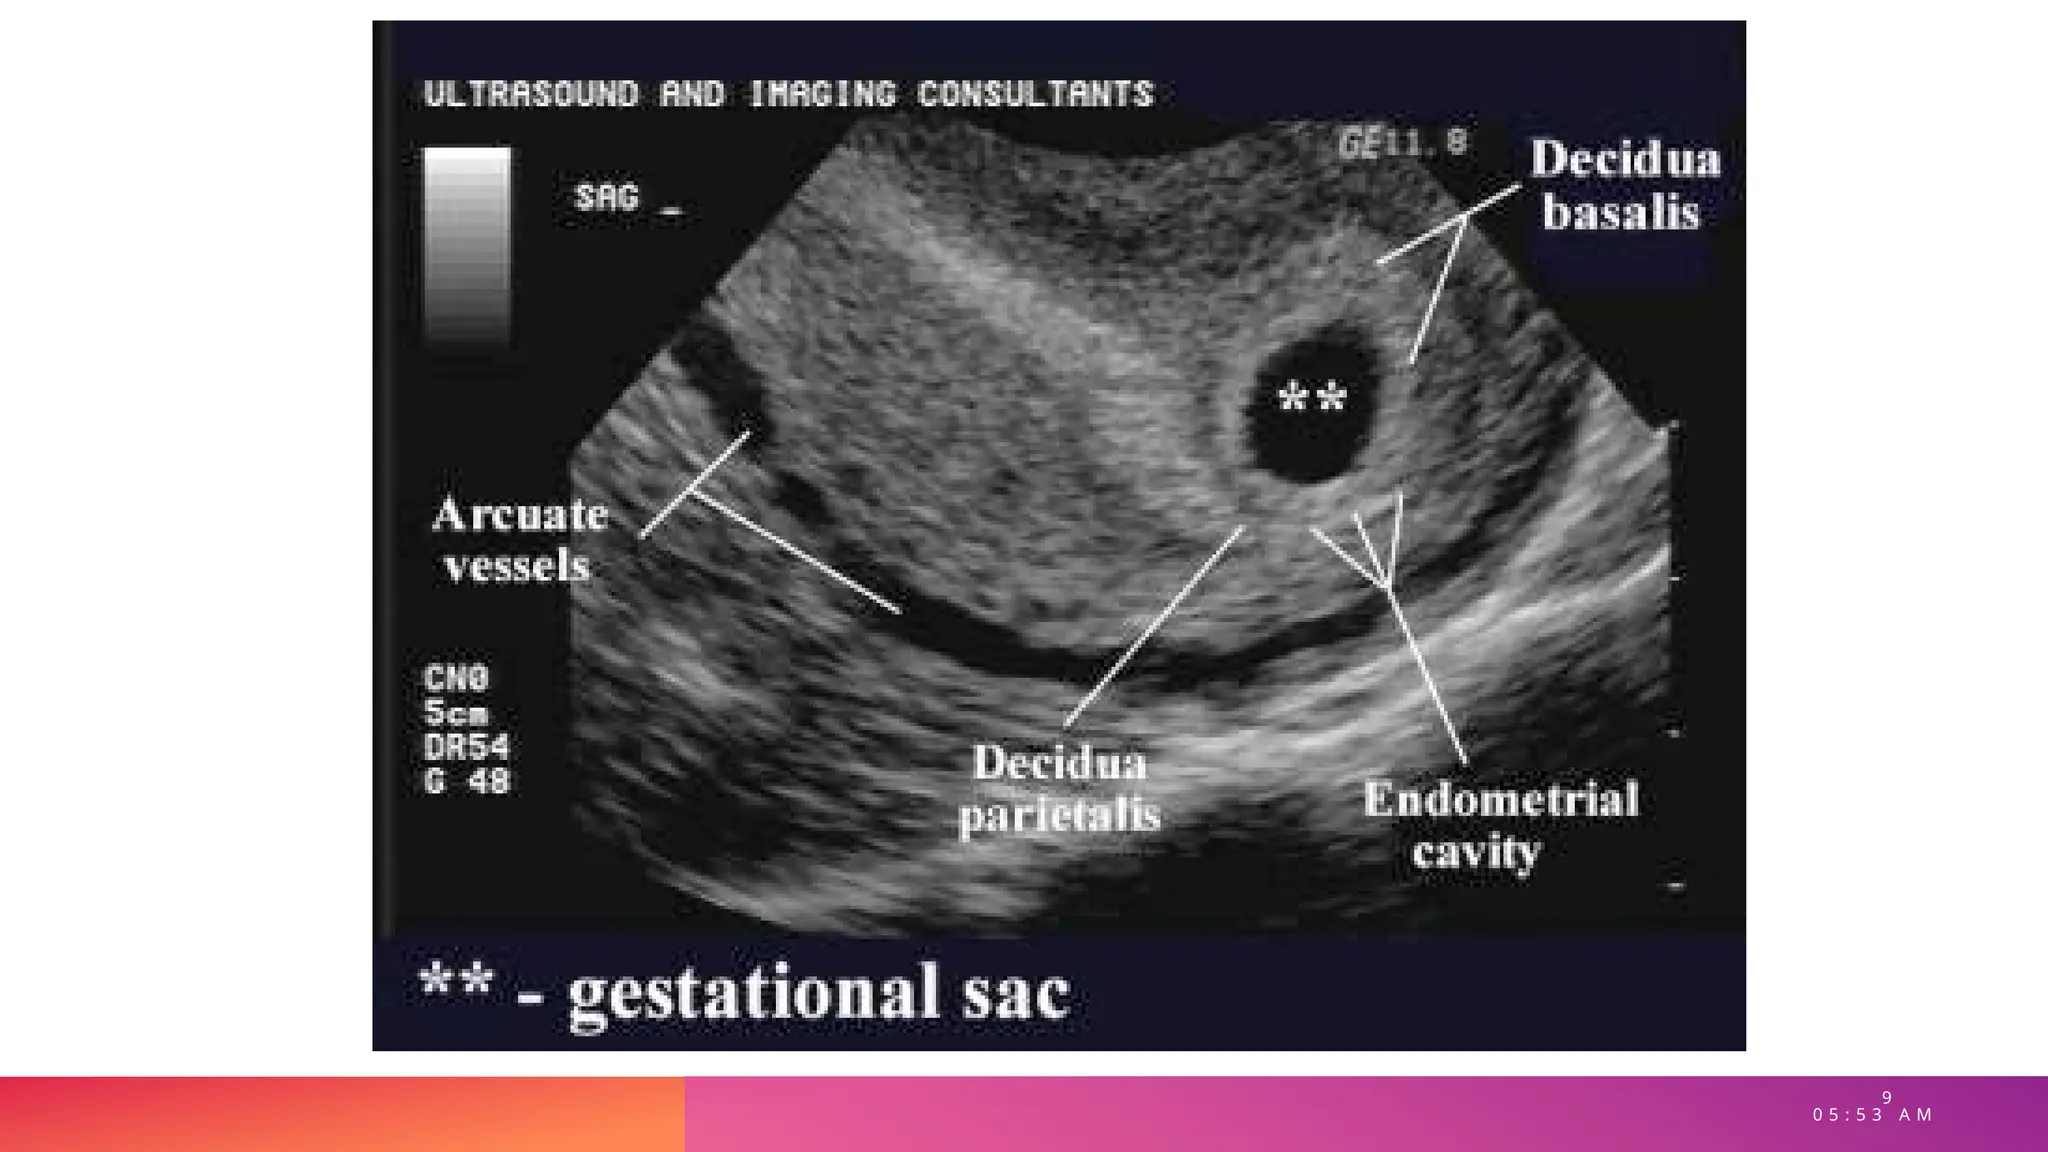

• SIGNO DOBLE DECIDUAL

• Diferenciación entre embarazo

intrauterino precoz y reacción decidual

secundaria a embarazo ectópico

• Dos anillos ecogénicos en la cavidad

endometrial

• Decidua parietalis : anillo externo, capa

decidual del útero

• Decidua capsularis: anillo interno, cubre el

margen libre del saco gestacional.

• Decidua basal: base endometrial del saco. +

corion frondoso : placenta.

Ecografía normal